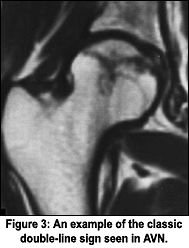

MRI is the most sensitive, noninvasive method for diagnosis of both TOH and AVN. Diagnosis involves detection of marrow foci of decreased signal on T1-weighted images and the characteristic double-line sign. The double-line sign is the differentiating sign for AVN. With TOH, there is diffuse marrow edema that is hypointense on T1 and hyperintense on T2. The double-line sign is seen on the conventional T2 sequences; the inner border of the peripheral band shows high signal in 80 percent of cases. This is called the double-line sign of avascular necrosis, and is considered to be pathognomonic of AVN. Various reports state that the inner "bright" signal is due to the reactive interface, or granulation tissue, between infarcted and normal marrow. Other authors have shown that by changing the phase and frequency direction, the position of the inner bright signal changes in some cases, such that the etiology is that of a chemical shift artifact. Regardless of the etiology in specific cases, recognition of the double-line sign is useful, since it is frequently characteristic of AVN.1-5